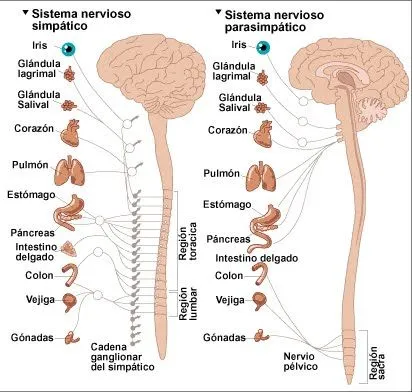

Dibujos del sistema nervioso central para colorear

Explora nuestra galería de dibujos del sistema nervioso central para colorear, ideales para aprender anatomía de forma didáctica y divertida.

Pix For > Sistema Nervioso Periferico Para Colorear

DIBUJOS DEL SISTEMA NERVIOSO CENTRAL PARA COLOREAR - Imagui

Sistema nervioso central y periferico para colorear - Imagui

Sistema nervioso central y periferico para colorear - Imagui